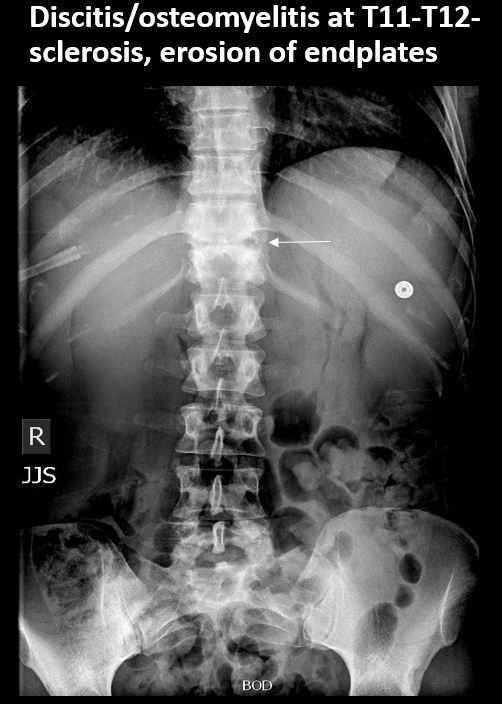

There is a lytic, blastic, or destructive lesion of the spine, pelvis, femurs, or ribs. [Yes/No]

There is abnormality of the discs, SI or hip joints, or pubic symphysis or other incidental abnormality of the pelvis. [Yes/No]